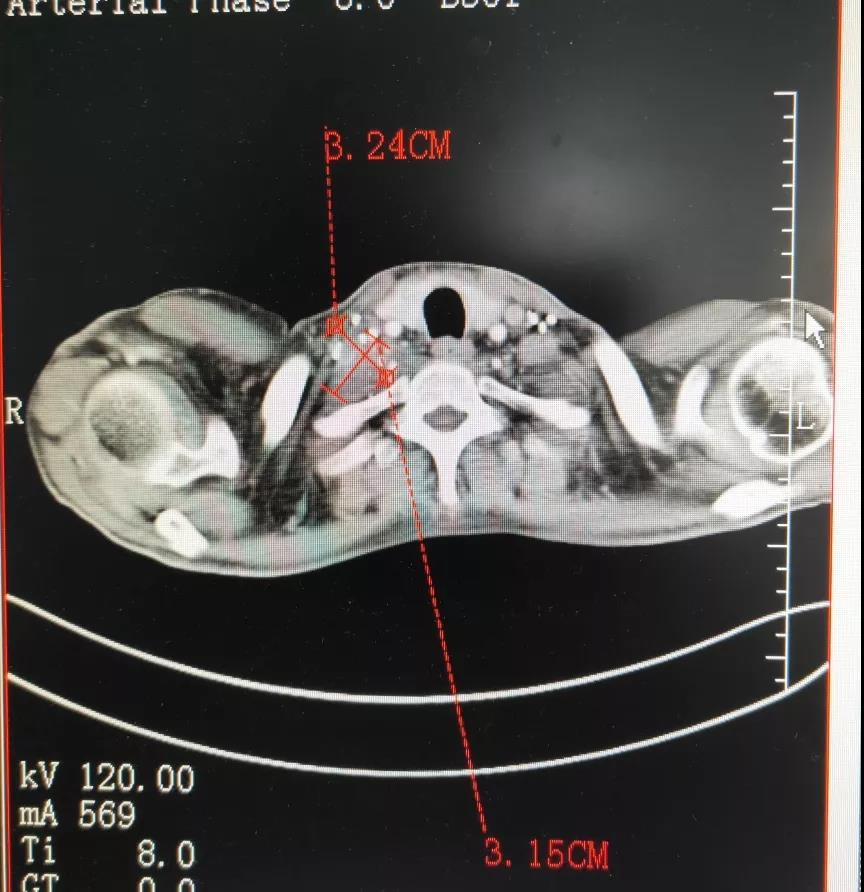

胸腺癌是一种罕见的纵隔恶性肿瘤,它如同潜伏在胸腔深处的阴影,悄然滋生于胸腺上皮细胞之中。最常见的组织类型是鳞状细胞癌和未分化癌,它们在显微镜下展现出与温和的胸腺瘤截然不同的狰狞面目——更具侵袭性的生物学行为。这种疾病尤其青睐成年男性,平均发病年龄在50岁左右,但也不乏特例:类淋巴上皮癌偶尔会侵袭儿童稚嫩的胸腺,而基底细胞样癌则偏爱中老年男性的躯体,黏液表皮样癌与腺鳞癌则可能在中老年女性体内悄然生长。

怀化深夜的诊室里,李教授捏着CT报告的手微微发颤——前纵隔4.2cm肿物,病理确诊为B2型胸腺癌。这种罕见肿瘤的治疗选择成为他最大的困扰。事实上,胸腺癌发病率不足恶性肿瘤的0.2%,能规范治疗的医疗机构屈指可数。专业胸...

怀化“体检报告里突然蹦出‘胸腺癌’三个字,是不是写错了?”这是35岁的阿杰拿到CT报告后的问的话。过去半年,他反复胸口闷、眼皮下垂,一直以为是加班熬夜累的。直到增强CT显示前纵隔4.2cm占位,医生才提醒:胸腺癌不是...